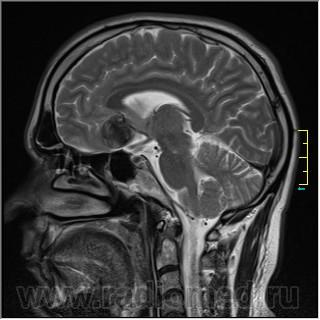

Sag T2:

частично функционирующая аневризма

Иначе говоря, аневризма с хронической геморрагией, т.к. мы видим фракции крови различного возраста.

По-моему, аневризма с пристеночными тромбами.

Постепенное пристеночное образование тромбов приводит к появлению типичного для аневризмы феномена -слоистости МР сигнала в полости аневризмы. Данная картина демонстрирует слоистый характер тромботических масс в полости аневризмы .Функционрирующая часть имеет низкий сигнал во всех режимах сканирования. Дополнительно-перифокальный отек.

А может более корректно интерпретировать как частично тромбированная аневризма... Уж коь речь идет о фракциях, ну то есть о тромбе по сути.... Ну и плюс перфокальный отек головного мозга (вероятнее цитотоксический+вазогенный).